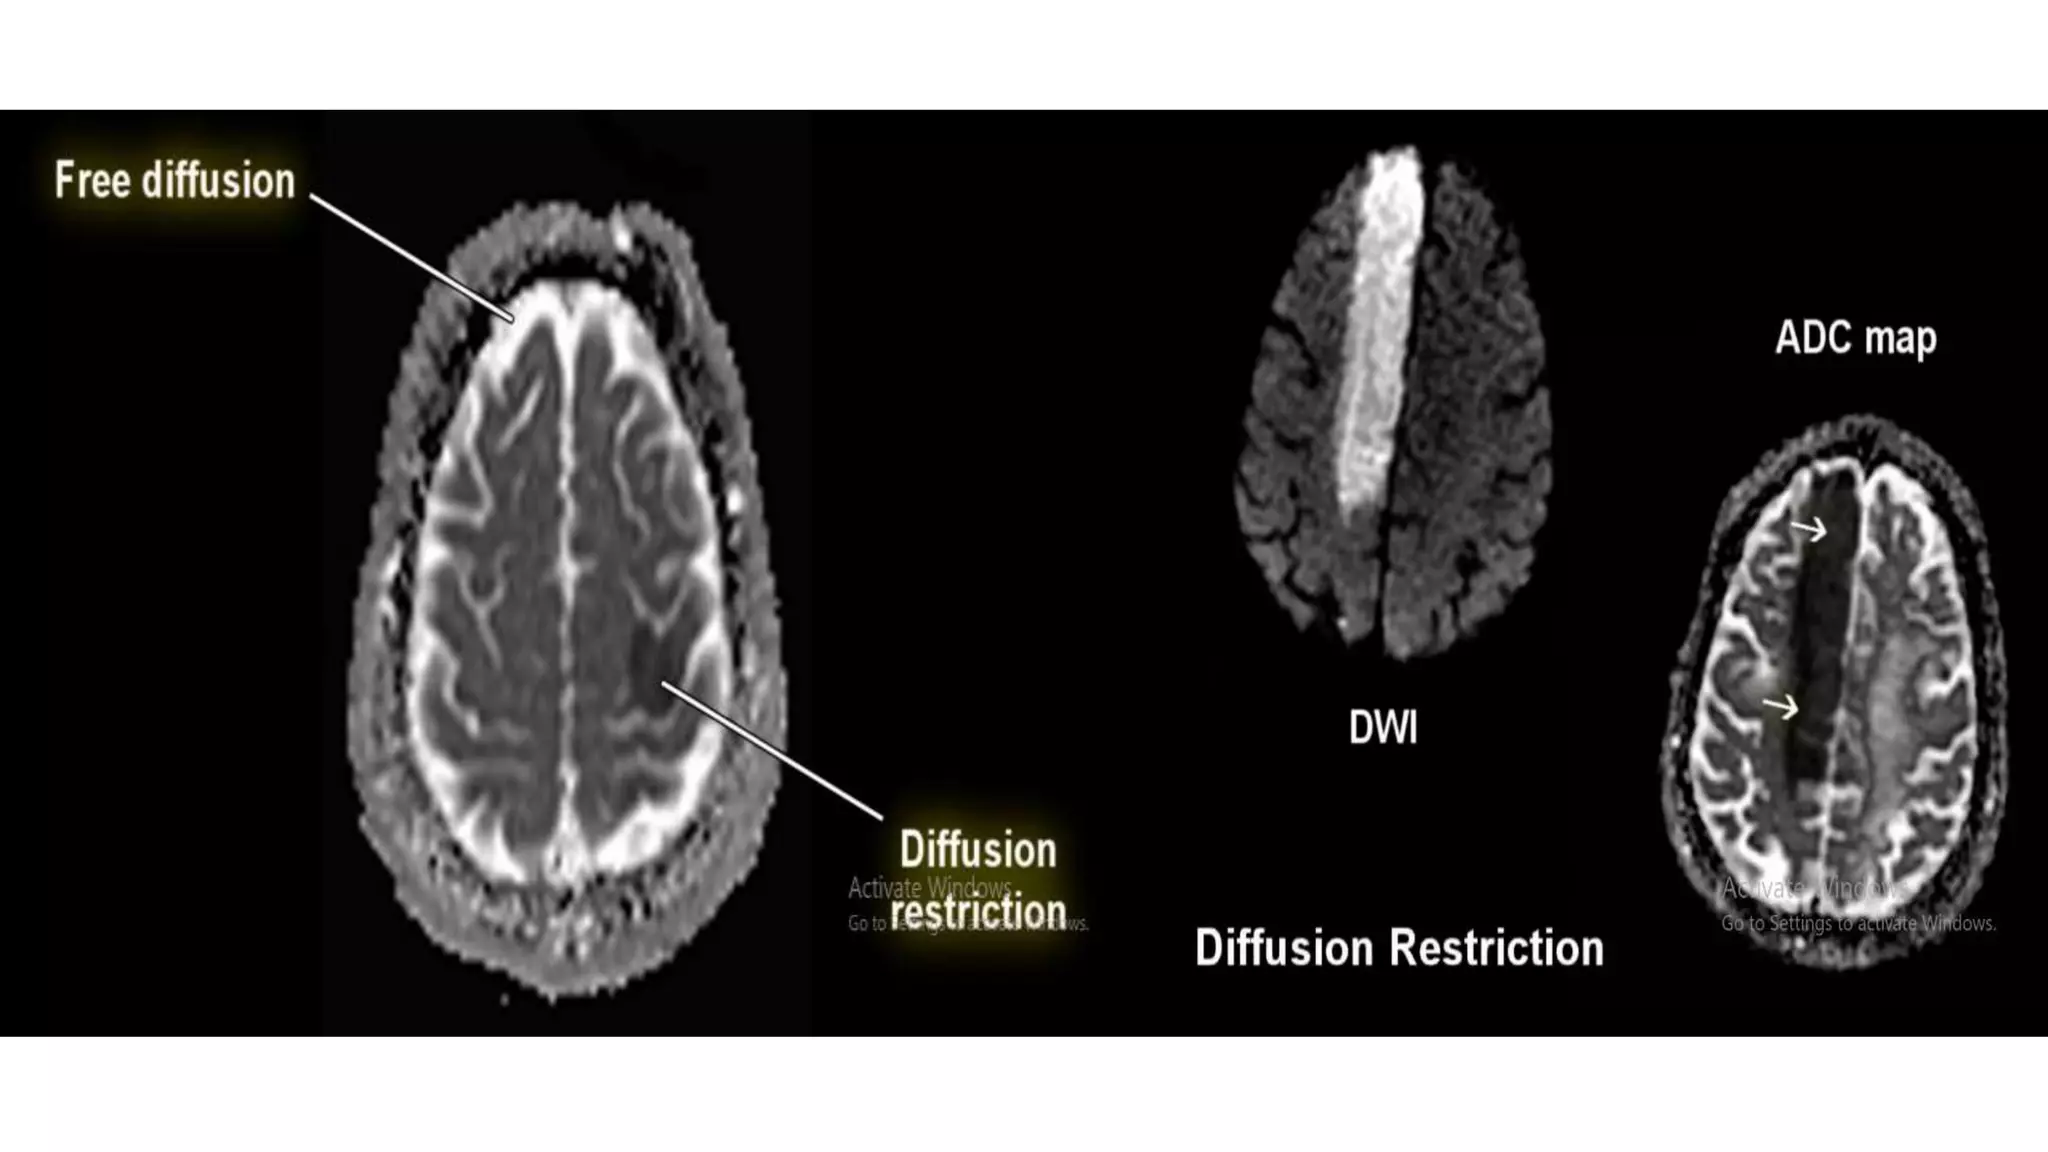

• Diffusion means random movement

of the water protons.

• The process by which water protons

diffuse randomly in the space is

called BROWNIAN MOTION.

• The difference in the mobility of

water molecules between tissues

gives the contrast in DWI and helps

to characterize tissues and

pathology.

• As the b value increases the signal from water molecule reduces.

• At high b value(b=1000) only tissues with very high T2 relaxation time or those

with restricted diffusion will have high signal.